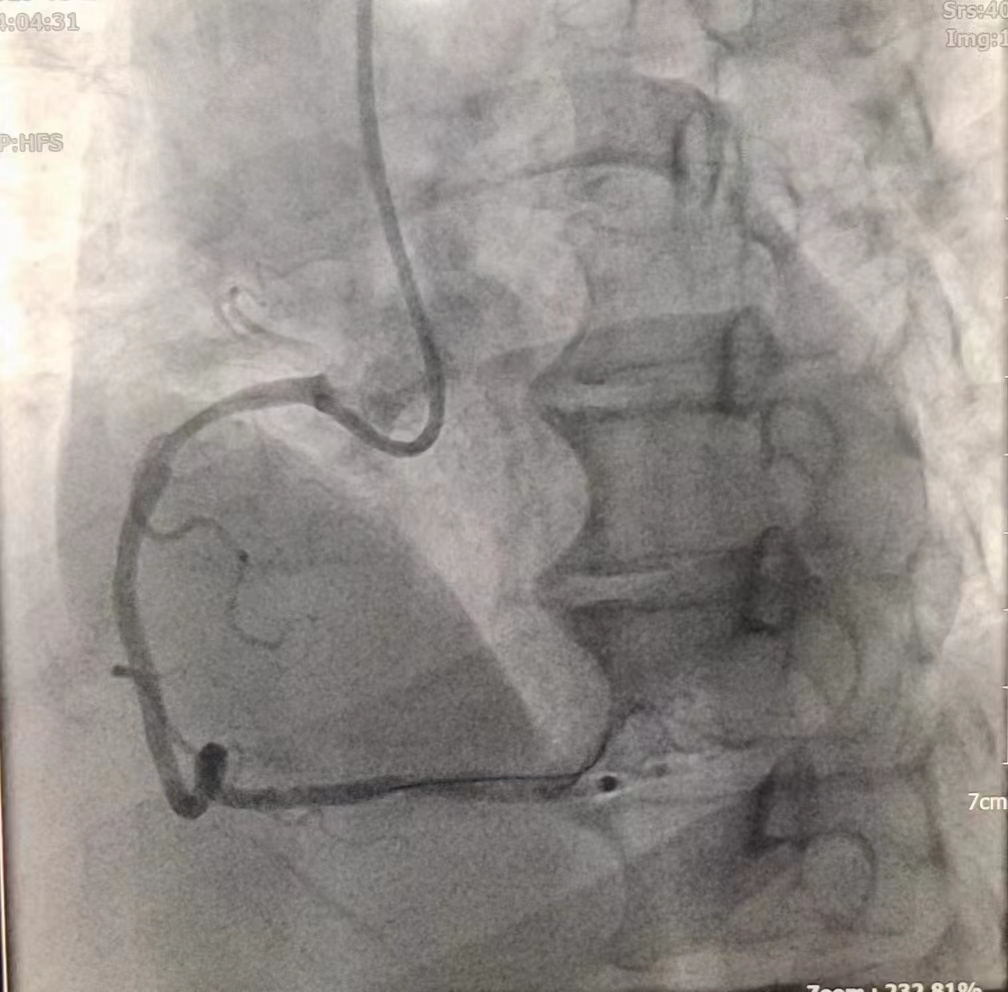

女性患者,49歲,突發暈厥急診我院,經診斷為:冠狀動脈粥樣硬化性心臟病、2型糖尿病。導入造影導管行冠狀動脈造影示:冠狀動脈分布呈左冠優勢型,LM未見明顯狹窄,血流TIMI3級;LAD全程多發斑塊,中段狹窄約60%,遠端狹窄約50%,D1未見明顯狹窄,血流TIMI3級;LCX未見明顯狹窄,血流TIMI3級,RCA近端狹窄約50%,中段發出圓錐支后完全閉塞,血流TIMI0級,急診開通血管并充分擴張,殘余狹窄仍然嚴重。在與患者及家屬溝通時,其了解得知臨床有一種新型的可吸收支架,植入體內后支架能完全被降解和吸收,希望能用這種新型的支架進行手術治療。由于生物可吸收支架有著嚴格的適應癥,因此經過嚴格篩選評估,最終對患者進行了Xinsorb生物可吸收支架置入術。支架植入術前經過充分預擴張,按照規范的可吸收支架操作流程,快速送入可吸收支架到病變部位,精準定位后14個大氣壓釋放,生物可吸收支架后擴球囊擴張。充分球囊后擴張,以保證支架貼壁良好,血流速度正常,造影完美,手術順利結束。

(圖為生物可吸收支架置入術后影像)